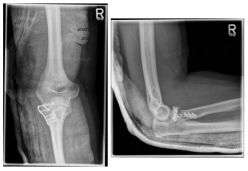

Photo: The fracture on the left is after an operation with a plate and screws |

If the image diagnostics performed (X-ray, CT) shows that a fractured bone part is displaced in the area of the joint surface (type II) or that the fracture is really present with several fragments (comminuted fracture (type III)), an operative therapy regime is required to restore the function of the radius head in the elbow joint. The extent of the surgical intervention depends on the extent of the fracture. While a fracture with only one displaced fragment can often be refixed with two small screws or a small metal plate, in a multiple fragment fracture situation it is often necessary to remove the complete radius head (resection) because reconstruction is no longer possible. This condition can be left if no instability of the elbow joint can be detected intraoperatively. If there is instability after resection of the radius head, implantation of a radius head prosthesis (artificial replacement of the radius head) is necessary.